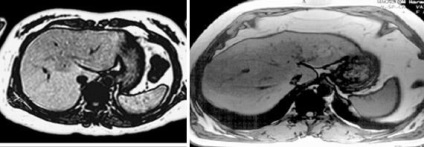

Cirrhosisos átalakulás a májban.

Haemochromatosis - máj-patológiai felesleges vasat a sejtekben a retikuloendoteliális rendszer. A betegség lehet primer (örökletes) vagy másodlagos - megemelt kézhezvételét vas a szervezetben (a transzfúzió utáni, a táplálkozási és mtsai.).